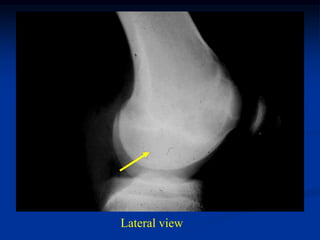

Case #556

55 year male with

enchondroma tibia

Lateral view